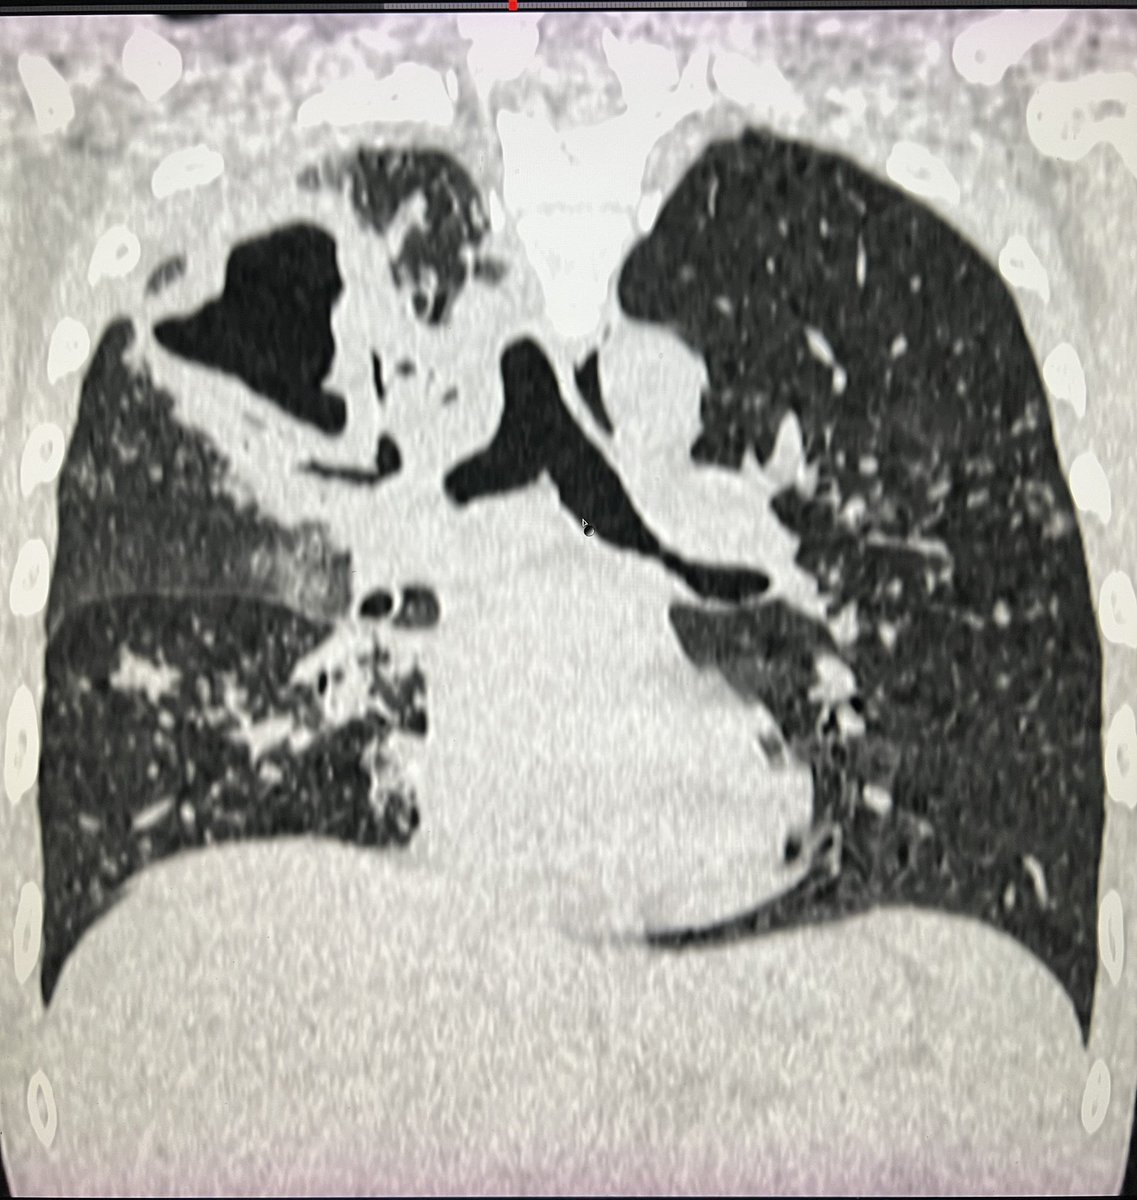

3 months

Active Pulmonary Kochs